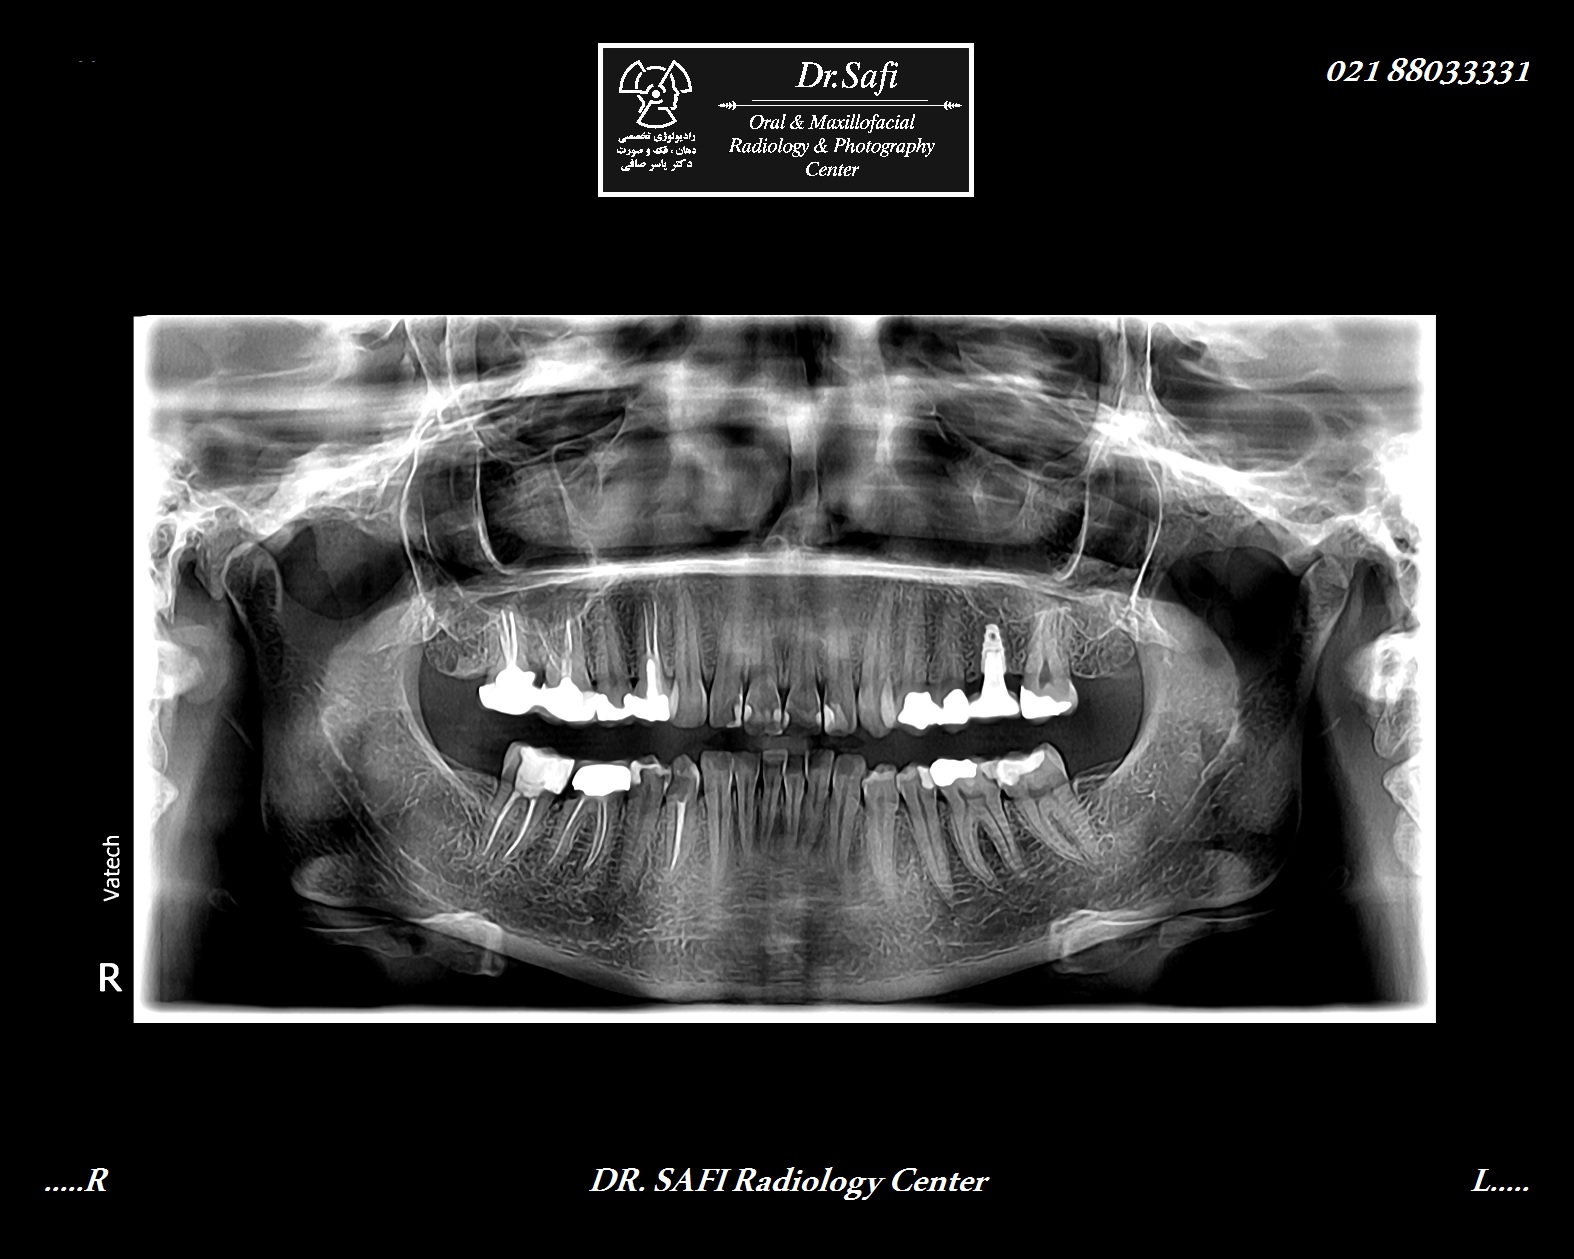

از رادیوگرافی پانورکس به منظور مشاھده کل دندان ھای روئیده و نھفته، مشاھده کل مندیبل و ماگزیلا، جھت ارزیابی تولیه کندیل ھا، جھت ارزیابی ارتباط فکین با ھم دیگر، جھت ارزیابی ارتباط دندان ھای عقل پائین با کانال مندیبولار و جھت مشاھده دندان ھای نھفته استفاده می شود. همچنین در مواردی که سن بیمار بیش از ھجده سال بوده و بدون سابقه کشیدن دندان، دندان عقل در دھان مشاھده نمی شود می توان از OPG استفاده نمود.

همچنین در موارد موجود پوسیدگی ھای متعدد و وسیع و در مواردی که به علت تریسموس، بیمار قادر به باز کردن دھان جھت تھیه رادیوگرافی داخل دھانی نمی باشد، OPG به کار گرفته است. همچنین قبل از گذاشتن انواع پروتزھای ثابت متعدد، در موارد وجود درد مبھم در دھان بدون وجود دلیل آشکار ، در موارد گذاشتن ایمپلنت ھای خلفی جھت بررسی کانال مندیبولار و سینوس ماگزیلا، در موارد وارد شدن تروما به فکین نیز می توان از OPG استفاده نمود.